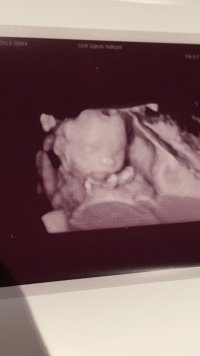

Så kjekt med 3D!Bekreftet gutt på OUL Så dere som gjetta hadde rett![]()

Jeg gjetter også tidlig jente, nuben kan reise seg endaNoen som vil gjette her? Tidlig ultralyd 12+2Vis vedlegget 415499

Spennende! Jeg skal oppdatere her når vi har vært på oulTidlig jente![]()